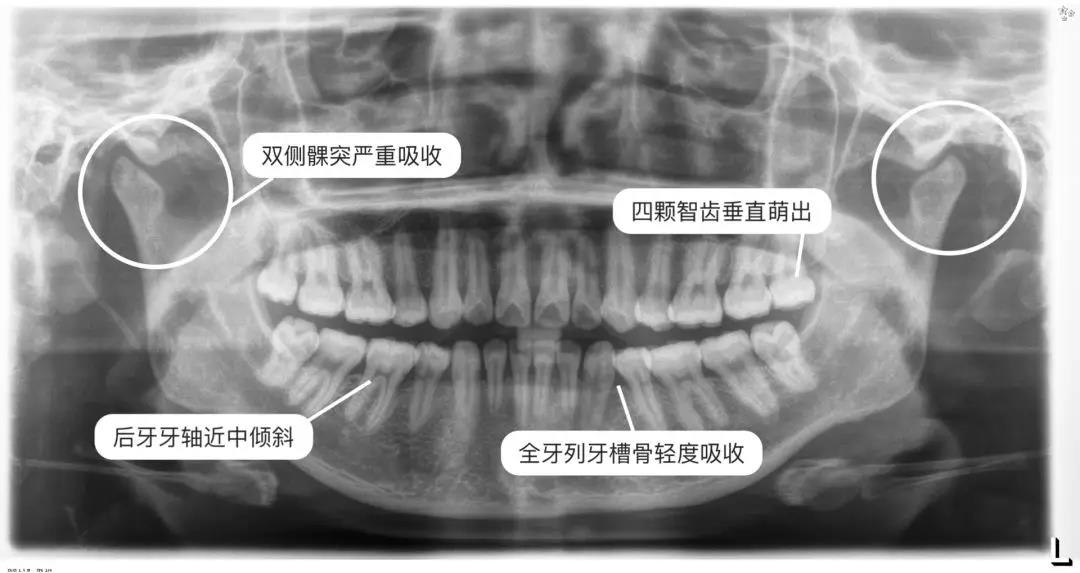

通過(guò)這兩張片子

醫(yī)師能夠?qū)δ愕难例X、牙根、牙槽骨、頜骨

甚至關(guān)節(jié)等進(jìn)行判斷、數(shù)據(jù)分析

看到一些肉眼無(wú)法發(fā)現(xiàn)的問(wèn)題